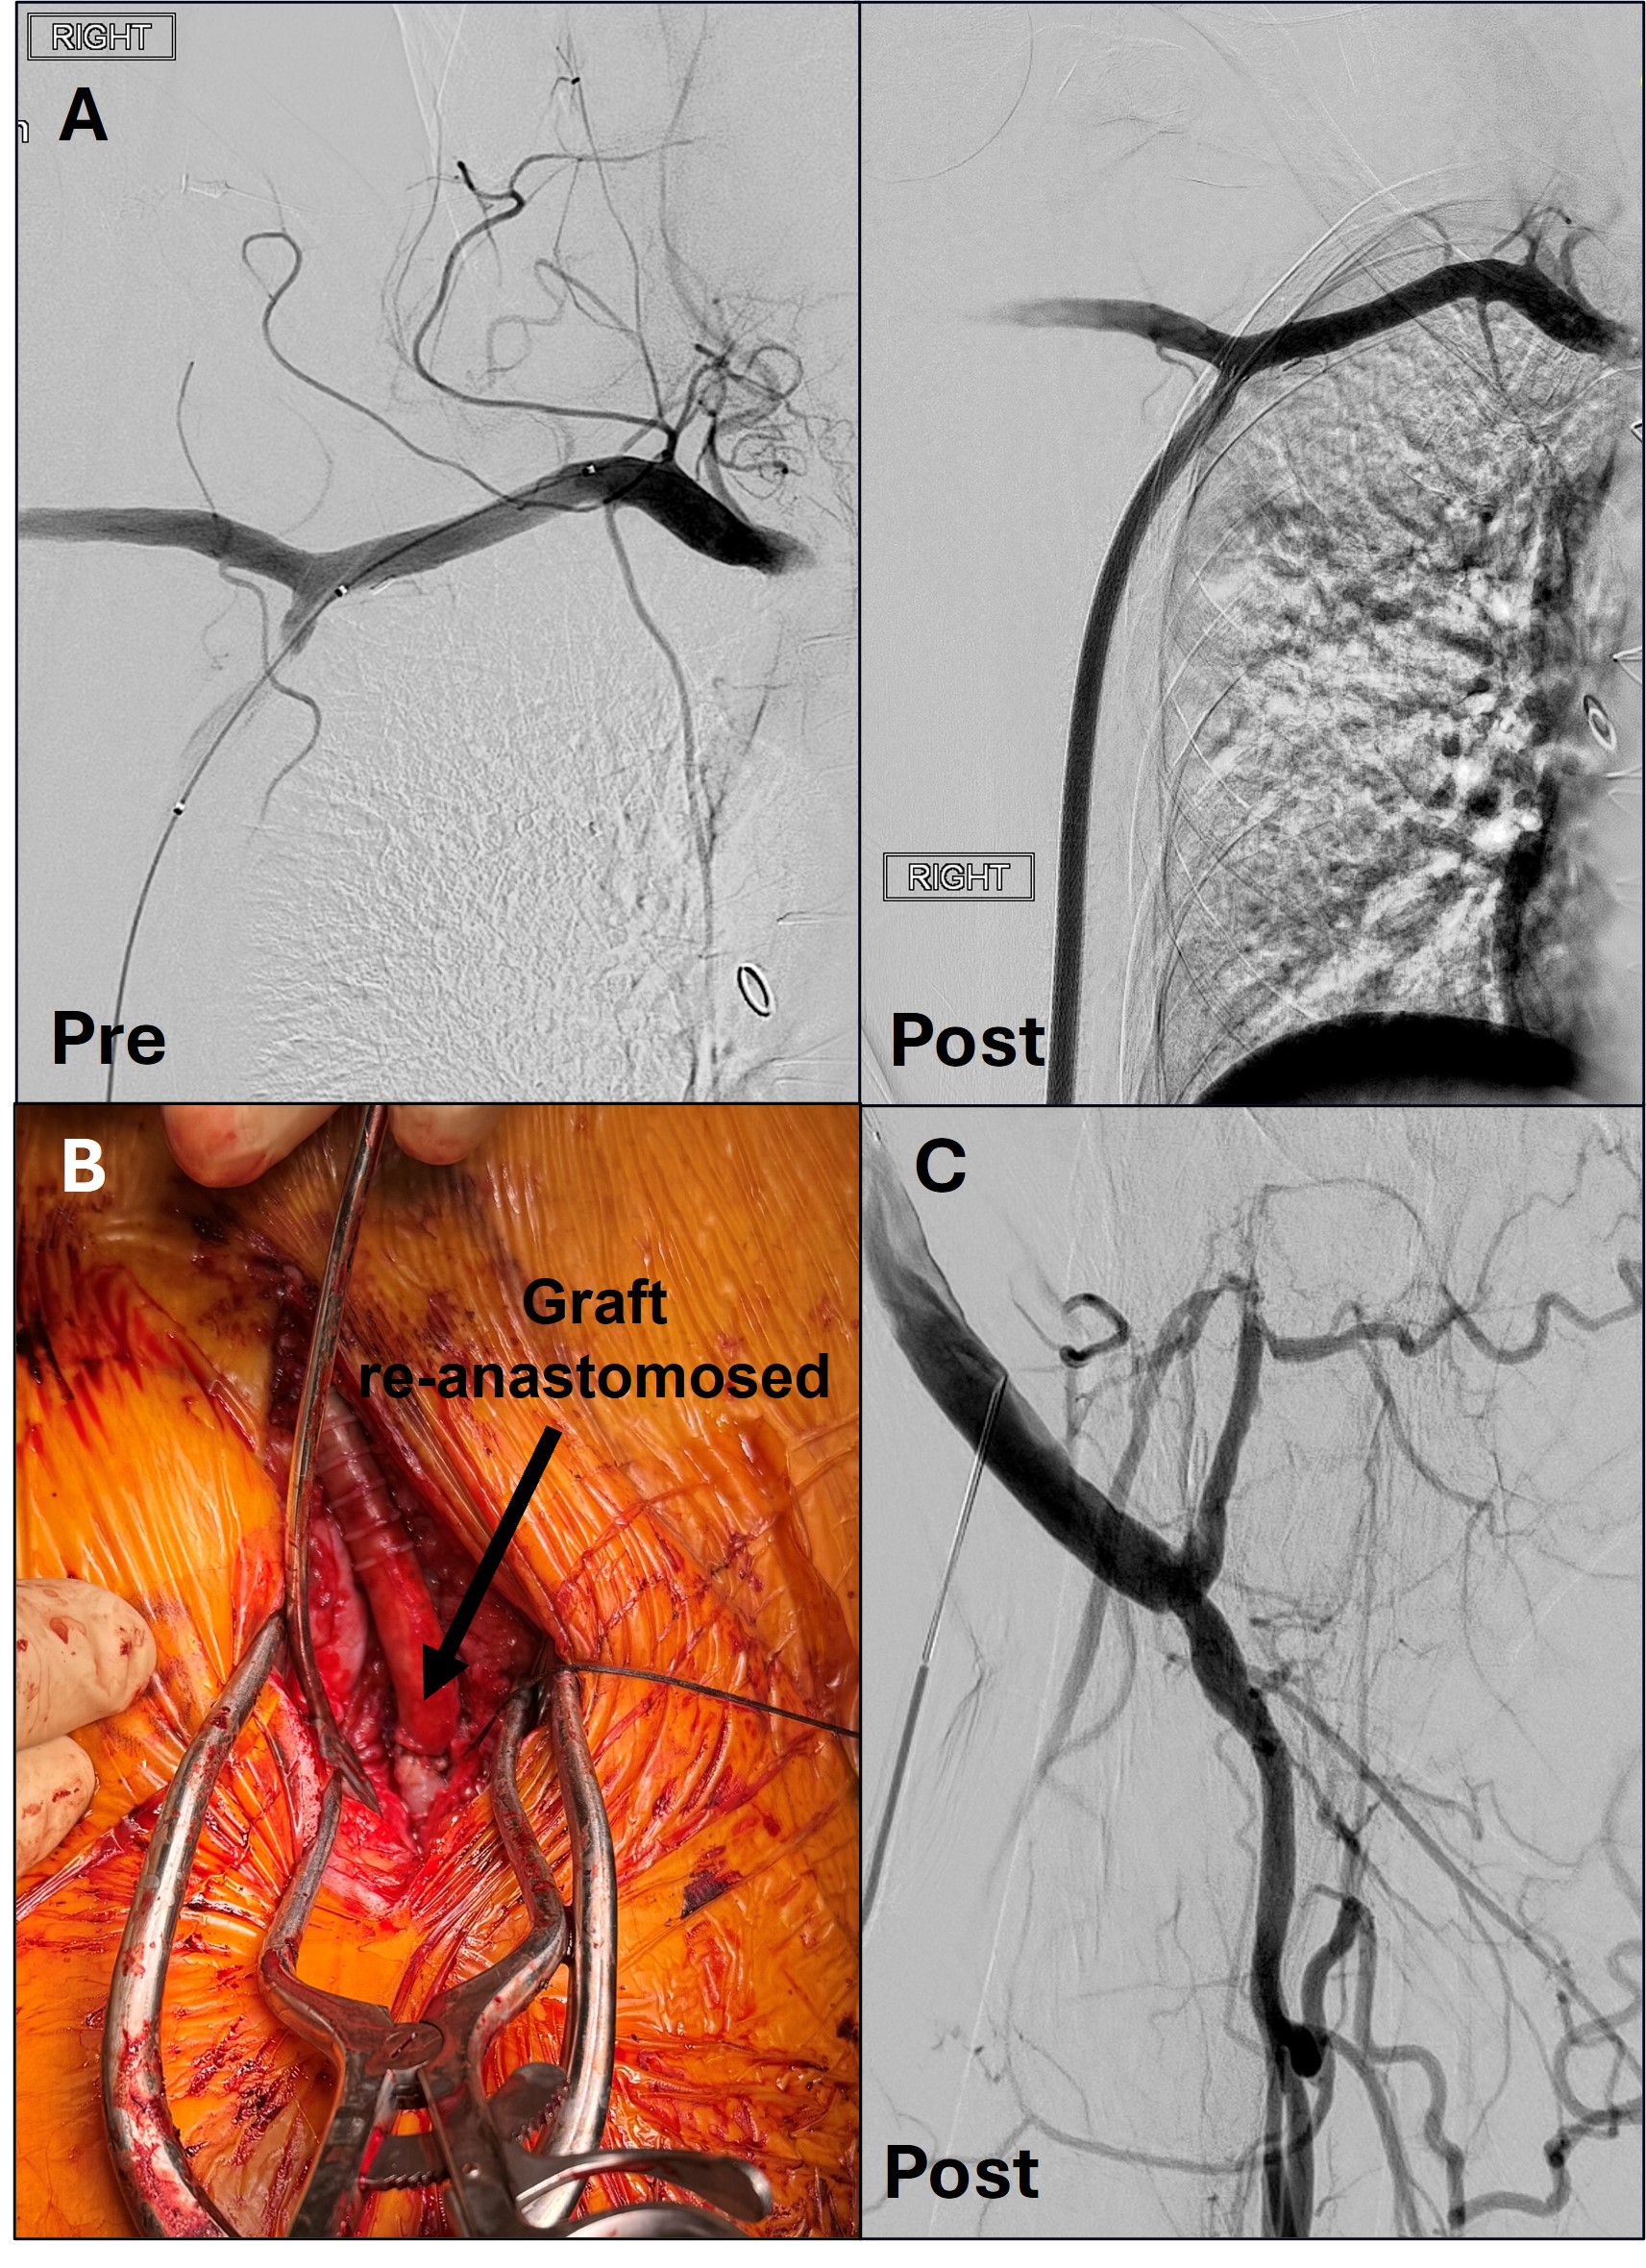

With the patient in a supine position under general anesthesia, a longitudinal incision of the right groin was performed. Systemic heparin was administered to maintain an activated clotting time of 300 seconds. Next, the profunda was exposed, and an incision was made at the graft anastomosis (Figure 2A). A 0.035-in Quick-Cross support catheter (Philips) loaded with a stiff Glidewire guidewire (Terumo Interventional Systems) was inserted and used to cross the long segment occlusion. After crossing, the guidewire was placed in the right axillary artery, then exchanged for a 0.014-in Mailman guidewire (Boston Scientific). An MT8 thrombectomy device, the mechanical component of the Artix system for vessels 4 mm to 8 mm in diameter, was inserted and advanced into the axillary artery (Figure 2B), where mechanical thrombectomy was performed through the entire graft.

Angioplasty of the graft with a 5 mm x 10 cm balloon was performed. A final pass with Artix yielded no thrombus, robust blood flow, and a strong palpable pulse. Angiography demonstrated a patent graft (Figure 4A).

To ensure the best odds of graft preservation given limited long-term options, 6 Viabahn stents (Gore Medical) were placed from the proximal anastomosis with adequate overlap down to the distal aspect of the graft. Next, patch angioplasty was performed on the mid profunda to improve outflow, and the newly patent graft was reattached to the profunda (Figure 4B). Completion angiography revealed a widely patent graft and profunda (Figure 4C). Doppler ultrasound confirmed flow restoration. Hemostasis was achieved, and the groin wound was closed.